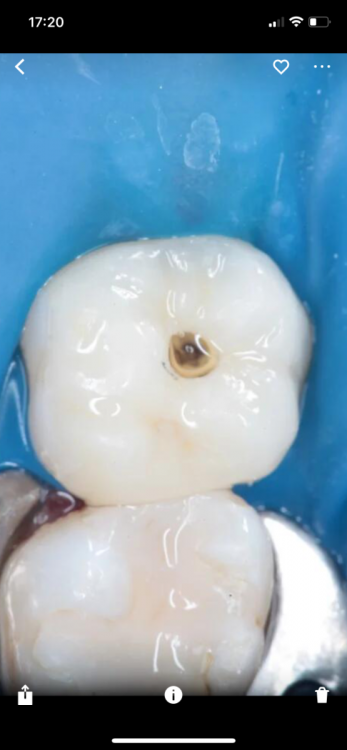

Гарриевич Опубликовано 3 мая, 2022 Автор Поделиться Опубликовано 3 мая, 2022 (изменено) Гемостаз и перекрытие мта гуттой Изменено 3 мая, 2022 пользователем Гарриевич 1 Ссылка на комментарий

Korabahtoff Опубликовано 8 мая, 2022 Поделиться Опубликовано 8 мая, 2022 Гутта из инжектора не обжигает пульпу? Ссылка на комментарий

Гарриевич Опубликовано 9 мая, 2022 Автор Поделиться Опубликовано 9 мая, 2022 7 часов назад, Korabahtoff сказал: Гутта из инжектора не обжигает пульпу? Гутта из инжектора идёт поверх мта, то есть не контактирует с пульпой Ссылка на комментарий